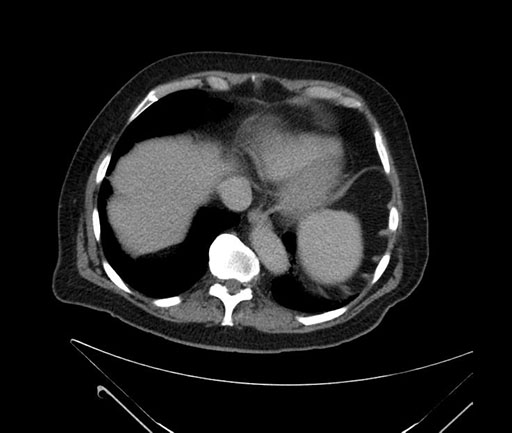

Whipple (pancreaticoduodenectomy) [case 7]

Imaging Analysis

Look through the patient's CT scan to identify any areas of concern for the necessary procedure.

Based on your CT findings, which issue(s) would give reason for "planned slowing down moment(s)" in this case?

Considering a standard Whipple procedure, what step(s) of the operation would you do differently in this case?